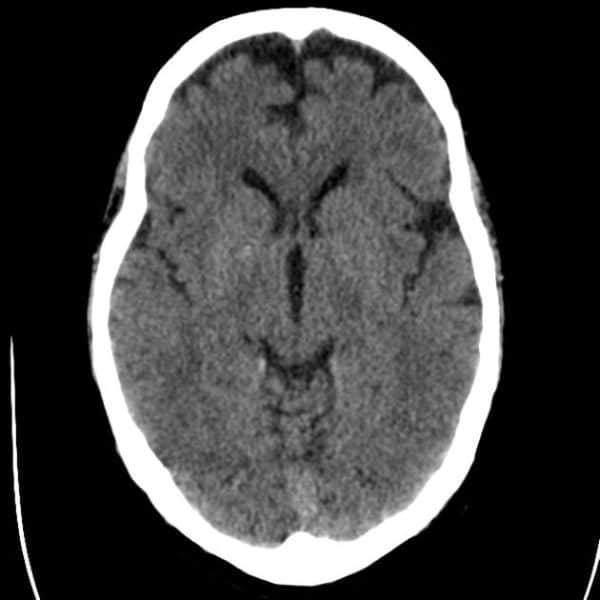

Nang vách trong suốt

Nang vách trong suốt - Ảnh 5

» Thông tin: Nam giới – 50 tuổi.

» Lâm sàng: Kiểm tra sức khỏe.